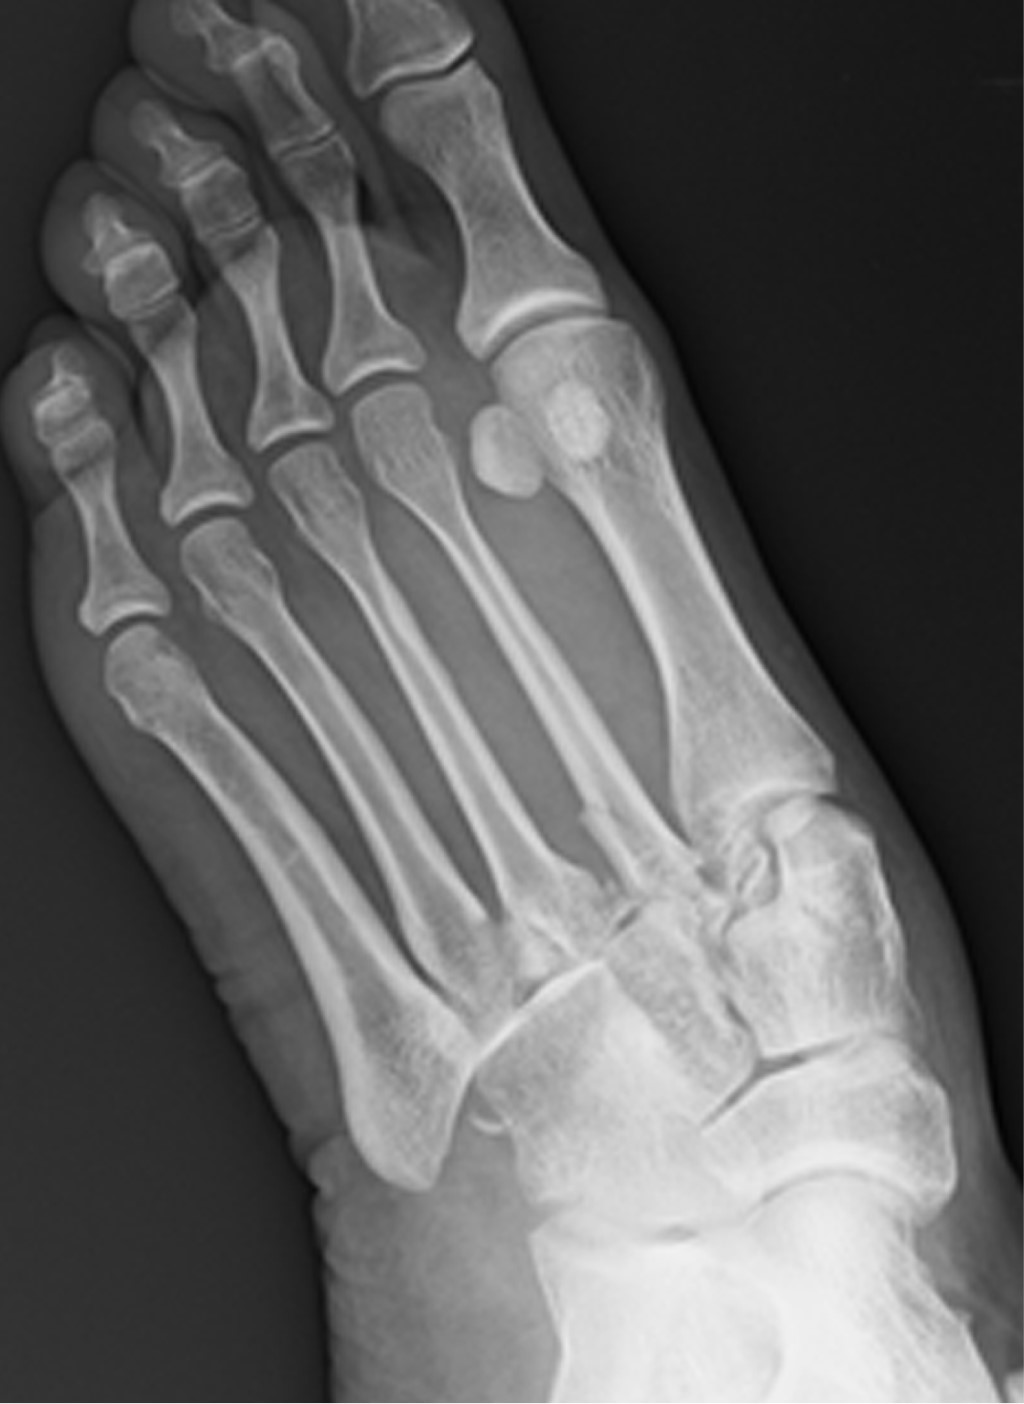

En cuanto al tipo de lesión, en el grupo de alta energía se observaron seis fracturas-luxación y una lesión ligamentosa pura. En el grupo de baja energía encontramos cuatro fracturas-luxación, una lesión ligamentosa pura y una lesión ósea pura (Figuras 1 y 2).

Figura 1